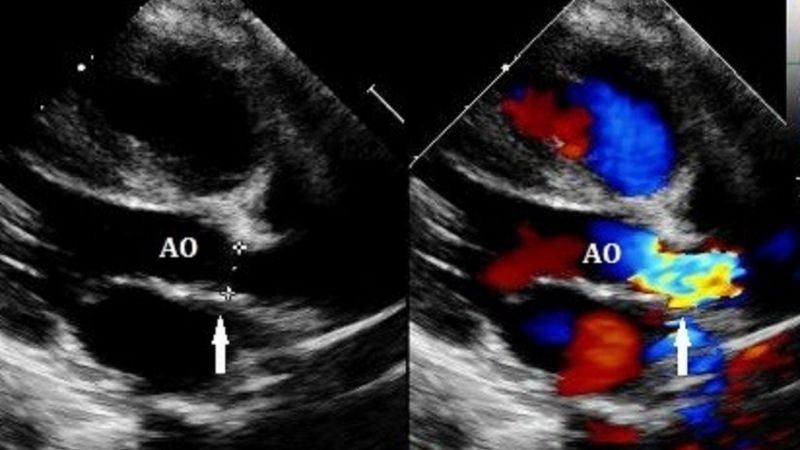

Shone's Complex is a rare congenital heart defect affecting the left side of the heart, often involving multiple obstructive lesions that impair normal blood flow.

Parachute mitral valve a unique congenital valve anomaly